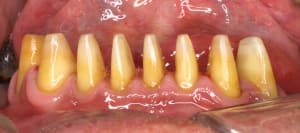

Mise en charge immédiate en 1 seul temps chirurgical avec le protocole Positdental.jpg